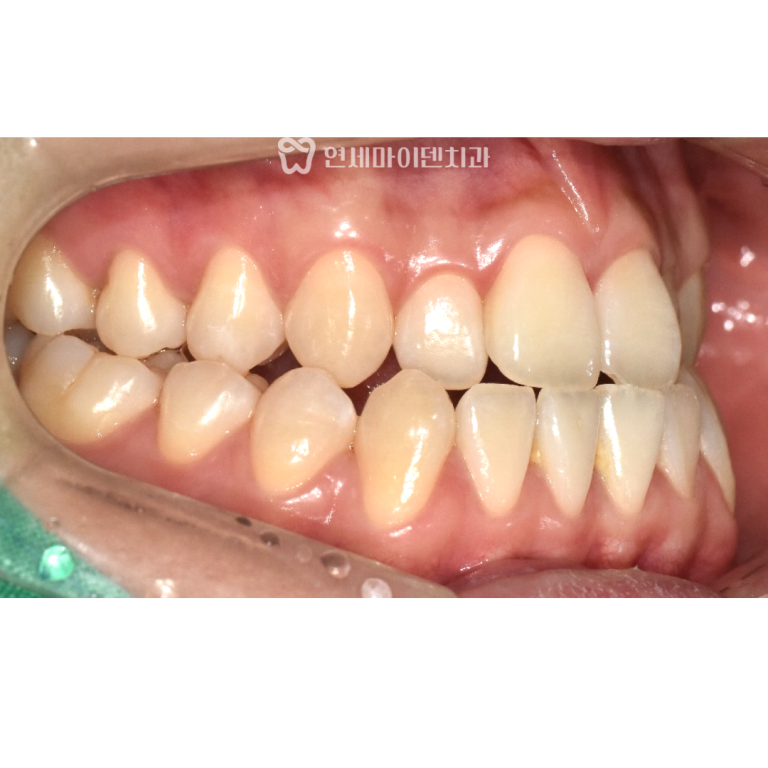

앞니 치료, 삭제 없이 레진 수복

이번 케이스는 임플란트 치료와 함께

깨지고 닳아진 앞니를

복구하는 치료도 필요했습니다.

앞니 교합 상태를 확인해보니

기존 라미네이트가

접착력 문제로 탈락하면서

심미적으로 불편한 상태가 된 것으로

판단되었습니다.

의료진 입장에서는

다시 라미네이트 치료를 통해

접착력을 확보하는 방법을

권해드릴 수 있었지만,

환자분의 비용 부담과

개인적인 선호를 고려해

복합 레진 수복으로

치료 방향을 결정했습니다.

앞니를 거의 삭제하지 않고

손상된 부위를 레진으로 메워

기능과 기본적인 심미를 회복하는 데

초점을 맞췄습니다.